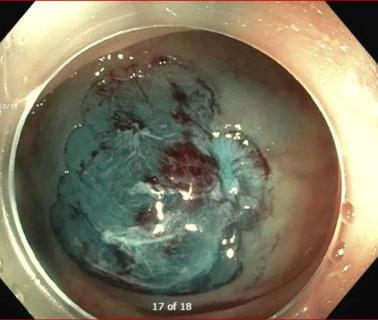

Colorectal Cancer Diagnosis Sequence has Surprising Impact on Outcomes

Cleveland Clinic researchers in Florida identify unexpected survival benefit